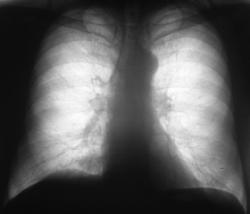

Пациент 76 лет жалоб не предъявляет. В 2006 году был направлен на профилактическую флюорографию.

Иллюстрация 1. Флюорограмма в прямой стандартной проекции. При анализе полученного изображения было констатировано усиление и обогащение легочного рисунка справа медио - базально. Было отмечено некоторое уплотнение тени правого корня в области тела. В остальном отмечены изменения возрастного характера.